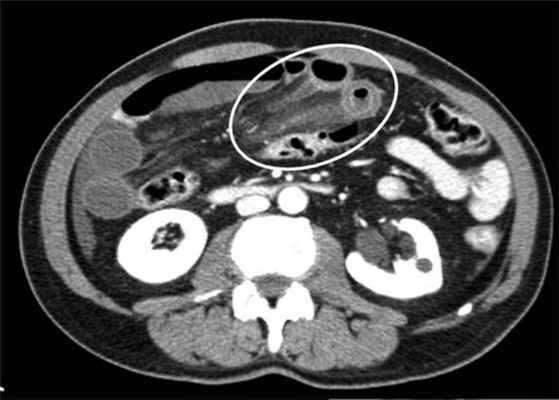

Осложнённая форма (чаще всего в результате странгуляции)

Для странгуляции тонкой кишки характерны утолщение стенок кишечника, васкулярные нарушения и выраженные патологические изменения в брыжейке и в брюшной полости. Диагностические находки включают в себя:

-расширенные петли тонкой кишки проксимальнее транзиторной зоны (зоны обструкции);

-спавшиеся петли кишечника дистальнее уровня обструкции;

-транзиторная зона;

-смешанный характер стаза содержимого кишечника в расширенных петлях с преобладанием жидкостного компонента;

-утолщение стенки кишки циркулярного типа. Важно помнить, такой тип утолщения стенок тонкой кишки при непроходимости как правило связан с сосудистыми нарушениями;

-нарушение нормального контрастного усиления стенок кишки. Изменения варьируют от гиперконтрастирования до полного отсуствия контрастного усиления. Различные варианты этих изменений между описанными выше крайностями могут наблюдаться одновременно в разных сегментах тонкой кишки. Полное отсутствие усиления означает артериальный рефлекторный спазм и свидетельствует в пользу тяжести поражения;

-петля с утолщенными стенками теряет свою эластичность и становится ригидной, вытянутой;

-пристеночный пневматоз тонкой кишки, в особо тяжелых случаях появляются интрамуральные пузырьки газа;

-появление патологических плотностей в брыжейке в виде распространяющихся матовых инфильтратов и тяжистости за счет кровоизлияний в жировые ткани;

-застойные изменения сосудов брыжейки. Сначала диаметр сосудов увеличивается, но со временем наступает рефлекторный артериальный спазм, брыжейка будет выглядеть с обеднённой васкуляризацией. Сосуды сужены или с полностью коллабированным просветом;

-газ в просвете верхней брыжеечной вены;

-газ в просвете портальной вены;

-при заворотах нарушается нормальная сосудистая анатомия брыжейки. Сосуды как бы закручиваются вокруг оси заворота и тянут за собой измененный брыжеечный жир- по типу раковины улитки или торнадо. Для большей наглядности представьте себе кусок расправленной ткани на столе, которую вы прижали пальцем и начали закручивать не отрывая ваш палец от стола. На КТ сканах часто можно увидеть характерный признак конусовидной спирали (whirl sign);

-свободная жидкость в карманах брыжейки и в брюшной полости. Иногда жидкость может быть повышенной плотности за счет геморрагического компонента.

примеры странгуляционной осложнённой непроходимости с характерными изменениями в брыжейке, внутрибрюшинном жире, утолщением стенок тонкой кишки и нарушением контрастного усиления.